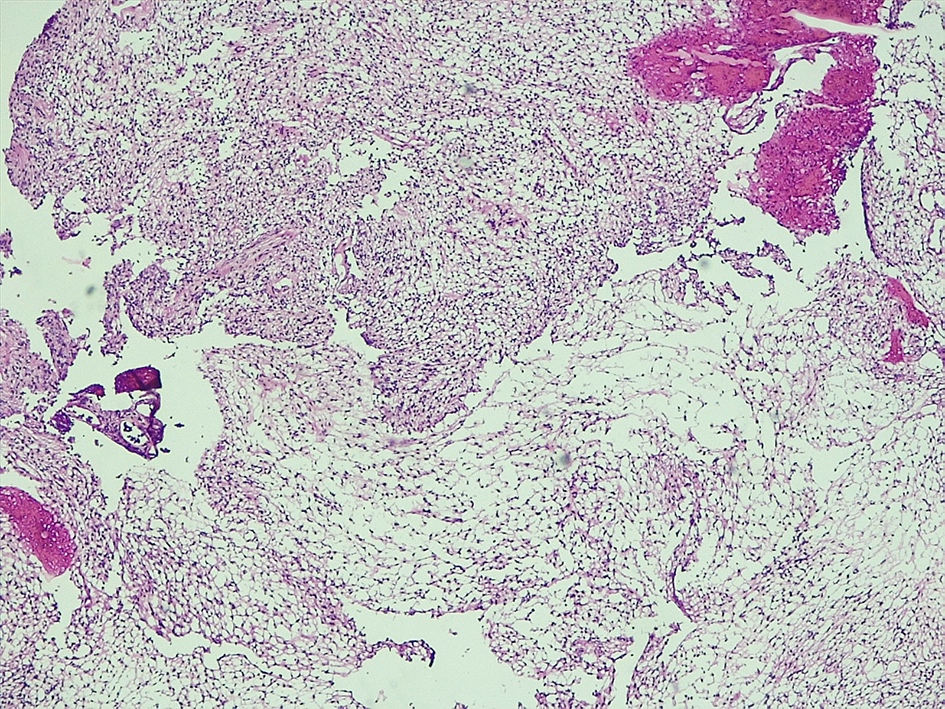

Microscopic (histologic) description

- Spindle cell tumor (usually biphasic) and composed of compact hypercellular areas (Antoni A tissue) showing nuclear palisading (Verocay bodies) and loose microcystic areas (Antoni B tissue) with collection of lipid laden histiocytes and thick walled hyalinized blood vessels (Surg Neurol Int 2020;11:454)

- Lymphoid aggregates maybe seen peripherally or in a subcapsular distribution

- Mitoses or focal degenerative atypia may be present

Microscopic (histologic) images